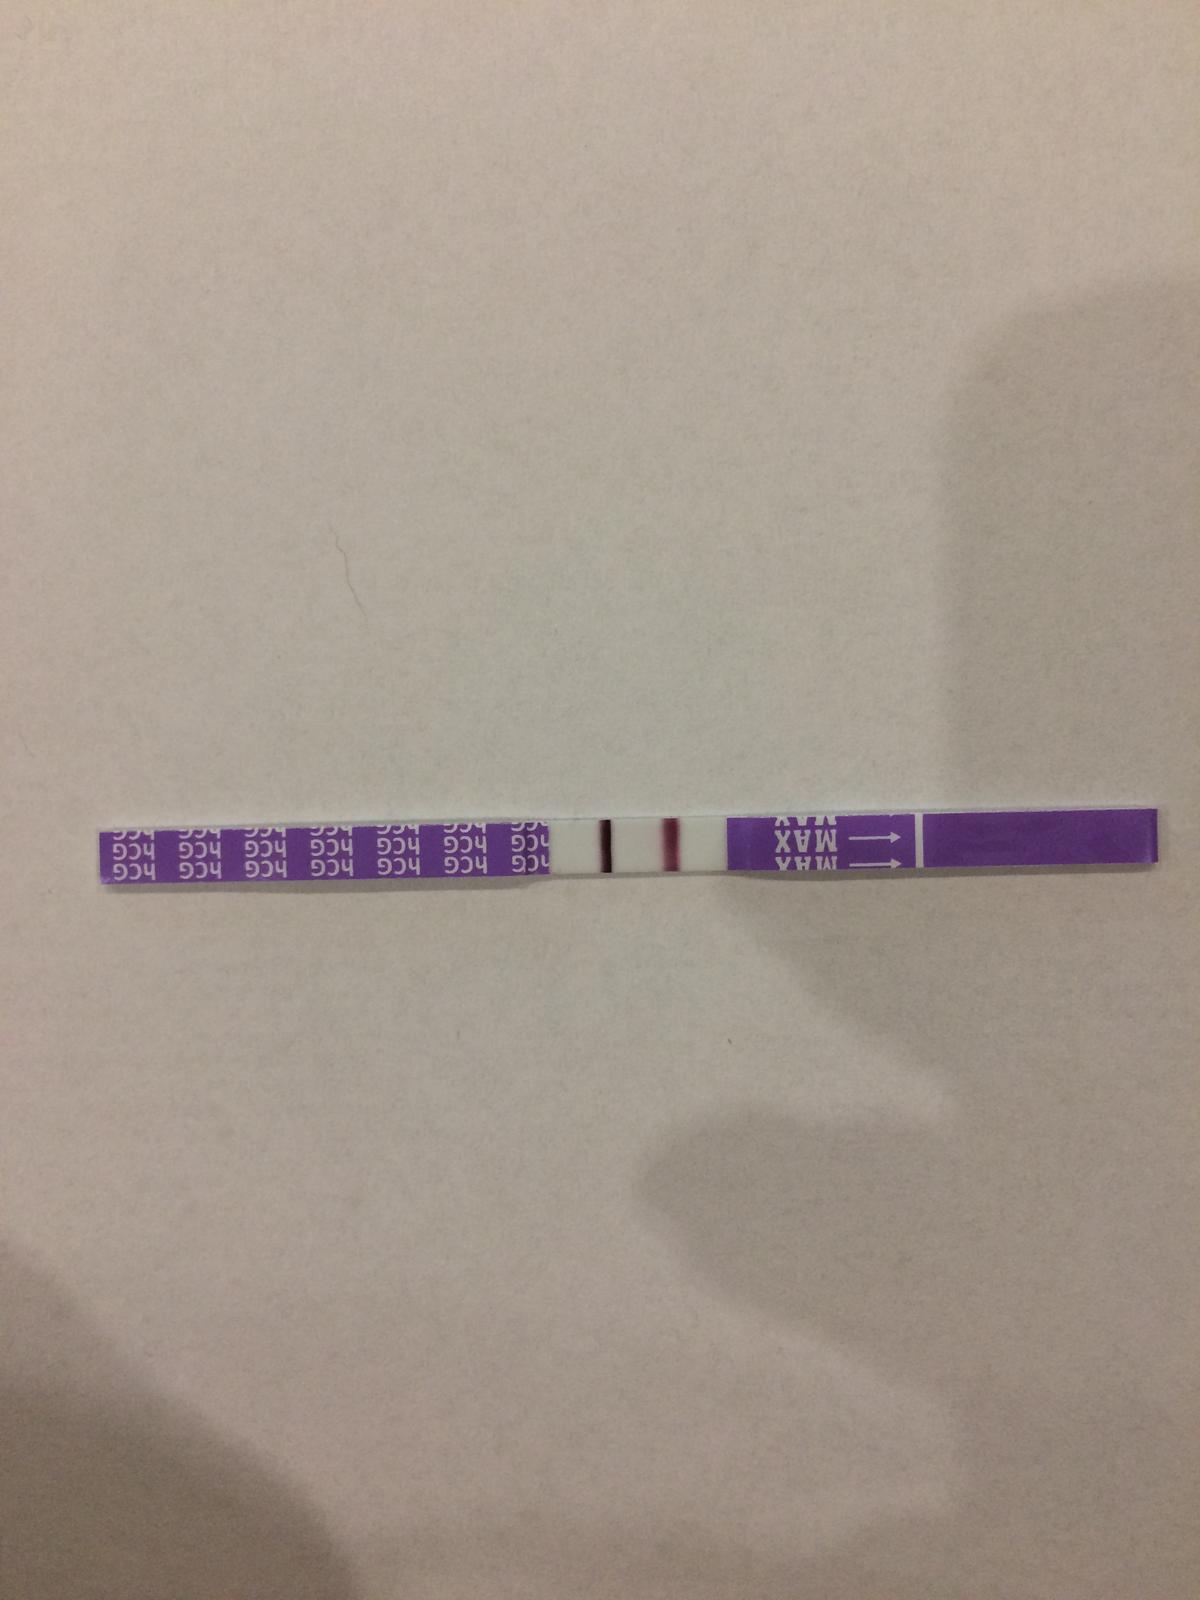

Krása, moc gratuluji!

Tak tomu se říká dálnice 😍 Gratuluji a ať je vše v pořádku ❤

Pořádná dálnice...Gratuluji

Silnější už být nemůže 🙂 gratulace veliká 🙂

Ty jo, to je dálnice. Moc gratuluju

Konecne nekdo kdo nelovi duchy😉

@marisse2428 teda to jsou pořádný čáry 😍

@leniczka23 já testovala dva dny po vynechání menstruace, tedy přesně to bylo 14dpo.. A stejně jsem měla čárku slabou 😀 takový čáry mám teď po 14dnech od vynechání..

@marisse2428 abys tam nakonec neměla dvojčata 😀 a moc gratuluju 🙂

@mariepas tak jasne..tak jsem to.nemyslela..spis ty dotazy vidite nevidite a jsou treba 9DPO.. proste nechapu testovani pred MS..

Je fakt ze ja 1 den vynechani taky nemela takovouhle dalnici teda..ale byla to viditelna carka..🙂

To budou dvojčátka 😍😃 Takhle silný test jsem mèla taky. A teď 36tt a čekáme dvojčátka. Gratuluji 🙂

@marisse2428 kolik dpo jsou tyto dálnice na testu?

@mariepas ja praveze neviem, kedy bola ovulacia. Ale mavam ju tak cca 14DC, ak by tak bolo, tak dnes je 15 DPO 🙂